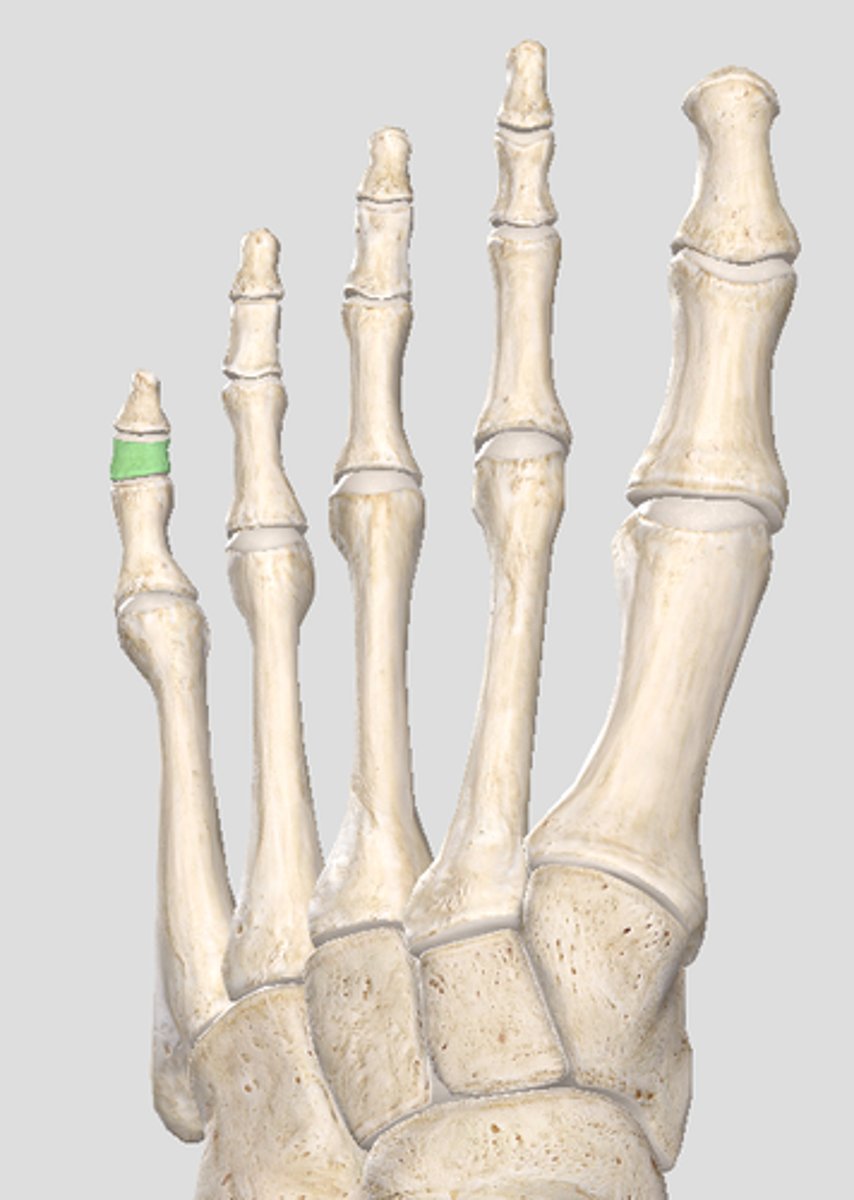

Medial articular surface (for medial condyle of femur; smaller)

green